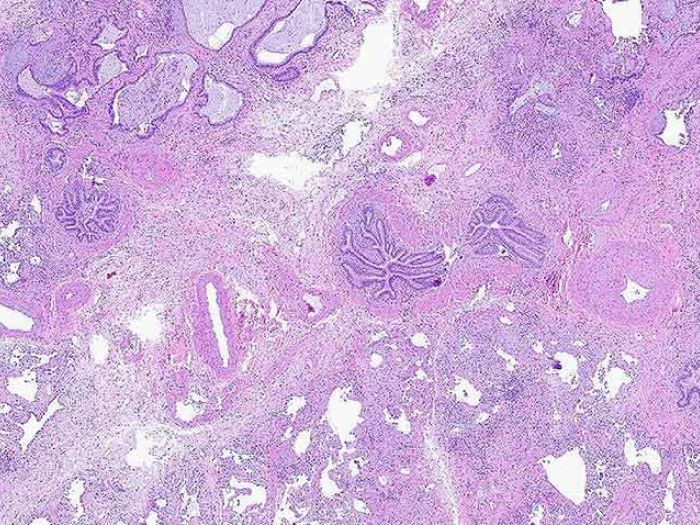

pink purple cellular microscopic slide

Health Lab

Pathologists find evidence of pre-existing chronic lung disease in people with long COVID

Some symptoms may be caused by damage developed before patients contracted the coronavirus.